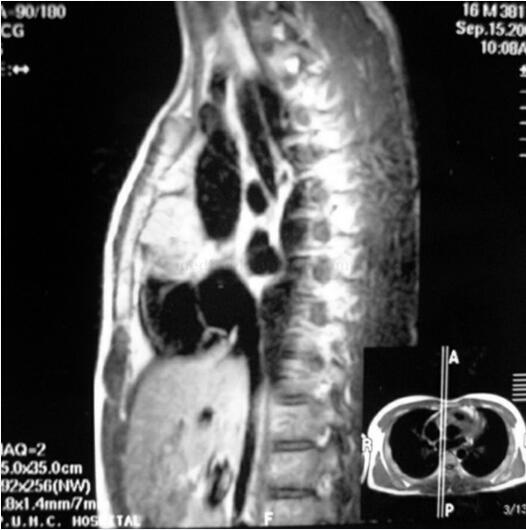

肾上腺CT未见异常;UCG未见心脏肿瘤;MIBG未见嗜铬细胞瘤征象;奥曲肽显像提示心脏内放射性浓聚区;再次复查UCG提示主动脉起始部前壁直径cm左右肿物,突出于右室流出道;CT示主动脉前壁肿瘤,与周围结构分界不清图31-1);MR(T2像)示主动脉前壁肿瘤,与周围结构分界不清(图31-2);冠状动脉造影(RCA)示右冠状动脉近段被肿物压迫闭塞,可见肿物血管影。

现病史:患者经超声心动图(UCG)发现心房内5cm×5cm肿物,查MRI证实心脏后下方肿瘤(图31-6)。诊断考虑“心脏肿瘤”于2003年11月在外院行手术治疗。术中见肿瘤源于房间隔,向左右房内突出,术后病理多方会诊为副神经节瘤,术后高血压明显缓解。术后两周查PET提示左房区域仍有代谢增高灶,术后1个月因心悸入我院,检查:心率150~170次/分,ECG示阵发性室上性心动过速,房室结折返,UCG房间隔回声增强,24小时尿儿茶酚胺基本正常,心脏T提示左房后下方见肿瘤(图31-7),MIBG(-),奥曲肽显像示左房部位异常放射性浓聚区临床症状轻,肿瘤基本无功能且呈地毯状生长。由于手术风险大,不考虑再次手术,仅因心律失常行射频消融治疗。

图31-6 MR(T2像)示心脏后下方肿瘤